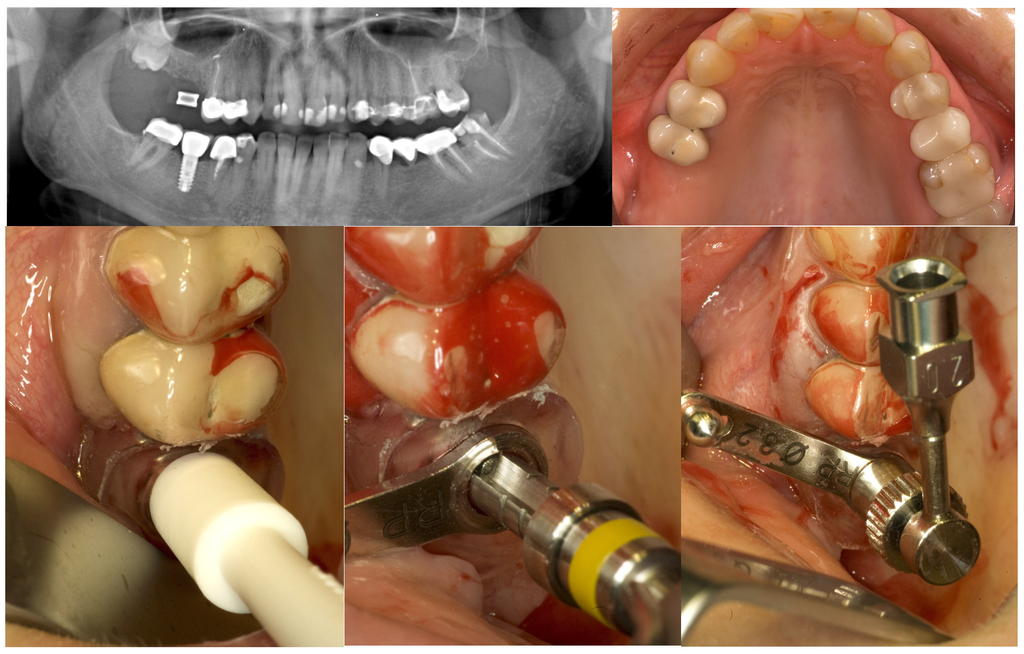

Figure 2.

GPT and implant placement in the right upper first molar region of a 43-year old woman.